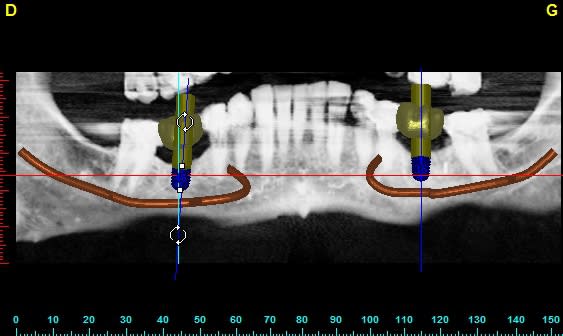

J'ai refait la planif.

Sur 46, un 8mm passera sans ROG -> 1/2 spire exposée ou peut-être une micro ROG.

Sur 36, il y a aura un peu plus surtout en lingual mais la quantité de matériau nécessaire est faible (peut-être que de l'os de forage).